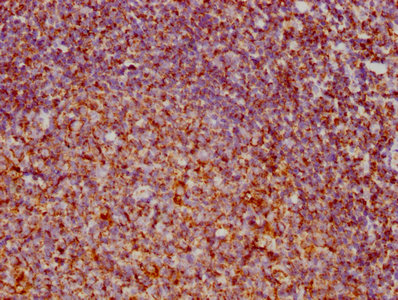

Flow cytometric analysis of IKK alpha expression in HepG2 cells using IKK alpha antibody. Green, isotype control; red, IKK alpha.

Immunocytochemical staining of HepG2 cells with component of inhibitor of nuclear factor kappa B kinase complex antibody. Nuclei were stained blue with DAPI; Component of inhibitor of nuclear factor kappa B kinase complex was stained magenta with Alexa Fluor? 647. Images were taken using Leica stellaris 5. Protein abundance based on laser Intensity and smart gain: Medium. Scale bar, 20 μm.

Western blotting analysis using IKK alpha antibody. Total cell lysates (30 μg) from various cell lines were loaded and separated by SDS-PAGE. The blot was incubated with IKK alpha antibody and HRP-conjugated goat anti-rabbit secondary antibody respectively.